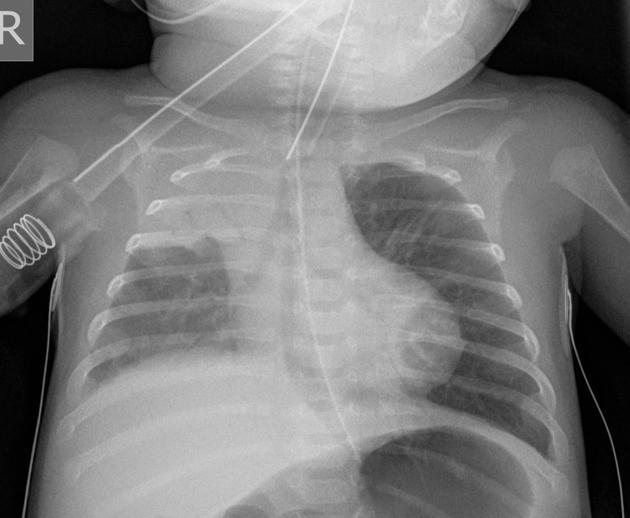

(right upper lobe consolidation)

In radiological studies ________ _______ presents as increased attenuation of the lung parenchyma causing obscuration of pulmonary vessels, without significant loss of volume, in the segment(s) affected. Air bronchograms can also be found

Lung Consolidation